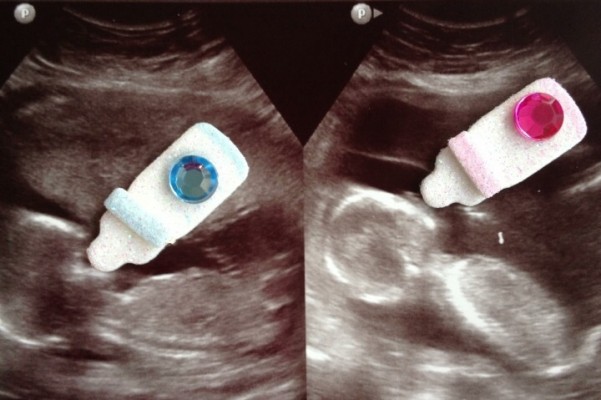

I am posting this story to help my brother in law, Delbert Perkins and his wife, Stephanie Perkins. They are expecting twins.

At 28 weeks they found out that the baby boy, Jessie Kole has a small hole between ventricles of his heart which will probably close on its own. Baby Girl, Annalise Claire has some severe cardiac problems, but they will be fixed with open heart surgery at birth. She will also be born with Down Syndrome.